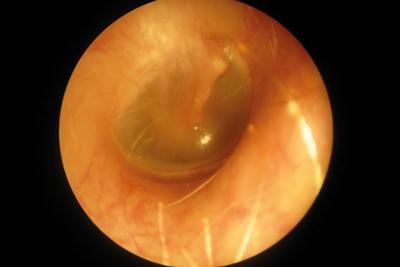

Endoscope-i - otoscopy image.

Endoscope-i **BEST VALUE**

Type: Endoscope adapter for iPhone 5/6/7/8/X (requires endoscope + light source) Captures images + videos

Cost: £99

Image quality: 87%

Field of view: 100%

Ease of use: 58%

Comments: Overall excellent image quality and field of view (tested with iPhone 7). Somewhat awkward for photo use due to the distance of the capture button from the endoscope attachment position. This resulted in a tendency for movement at the moment of photo taking. This was not a problem for videos which could be started and then a more comfortable grip found.